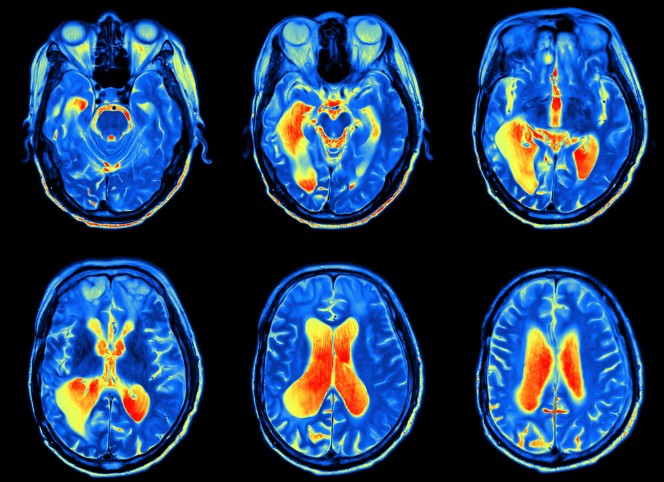

- Neuroimaging (MRI, CT, PET scans)